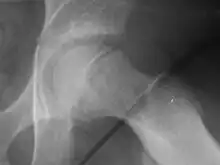

Line of Klein

Radiogram of slipped capital femoral epiphysis

Klein's line is a virtual line that can be drawn on an X-ray of a child's hip parallel to the upper edge of the femoral neck. If the line does not intersect with the outermost part of the femoral head 's ball-like end, the diagnosis of a slipped capital femoral epiphysis (SCFE) is confirmed.[1]